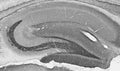

| 29209227 | not listed | Jalali, R., et al. 2017. The Role of Na:K:2Cl Cotransporter 1 (NKCC1/SLC12A2) in Dental Epithelium during Enamel Formation in Mice. Frontiers in Physiology, 924. |

| 27752731 | not listed | Bronckers, A.L., et al. 2017. Reduced Protein Expression of the Na+/Ca2++K+-Exchanger (SLC24A4) in Apical Plasma Membranes of Maturation Ameloblasts of Fluorotic Mice.. Calcified Tissue International, 80-86. |